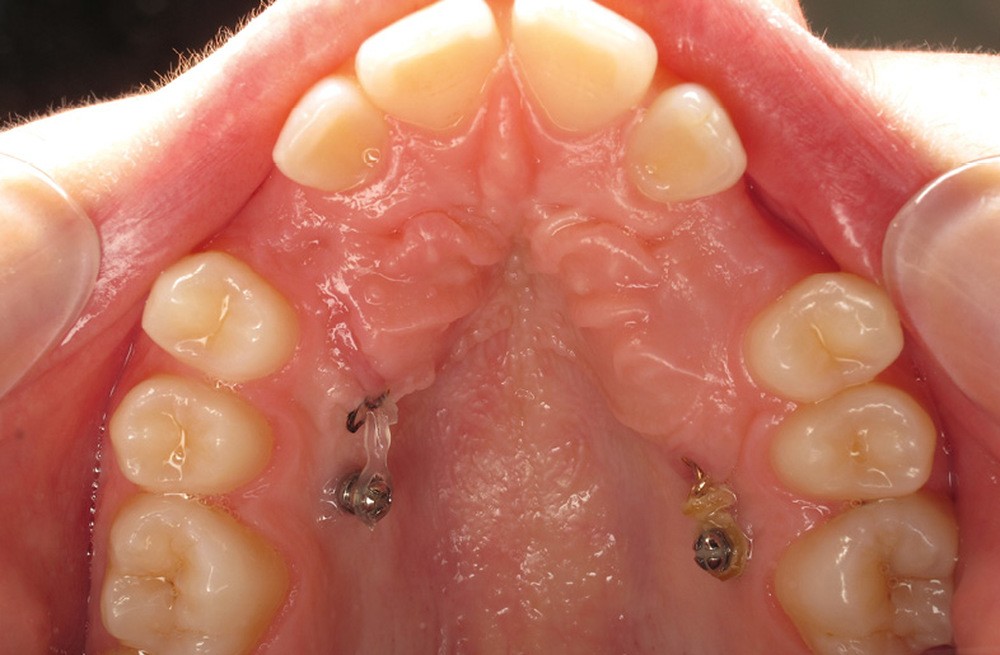

À côté de la coopération moindre qu’ils exigent, les ancrages squelettiques présentent également l’avantage de répondre à des indications très variées : correction des sourires gingivaux (Dr Skander Ellouze, fig. 3a-c), distalisation ou mésialisation molaire, supports pour les masques faciaux, mini transpalatin sur vis après expansion, ressorts de rétraction pour mettre en place les canines incluses sans léser les racines des dents adjacentes [3] (Dr Stéphane Renger, fig. 4) ou appareils d’expansion maxillaire (Dr Hans Winsauer, Dr Guido Sampersmans, fig. 5a-c)…

Le Dr Paul Cresseaux présentera dans un premier temps un ancrage squelettique, simple et efficace, développé par ses soins, pour optimiser la préparation orthodontique des classes II squelettiques : l’Abalakov (fig. 13a-d). Puis, il défendra la prise en charge simultanée, au cours d’un unique temps chirurgical, de l’ensemble des anomalies squelettiques présentées par nos patients.